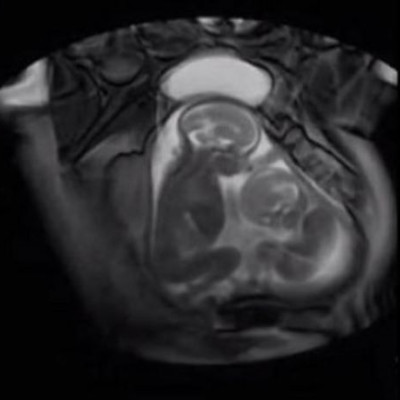

Δείτε δίδυμα μωρά να τσακώνονται μέσα στον πλακούντα. Ένα βίντεο που δεν έχετε ξαναδεί!